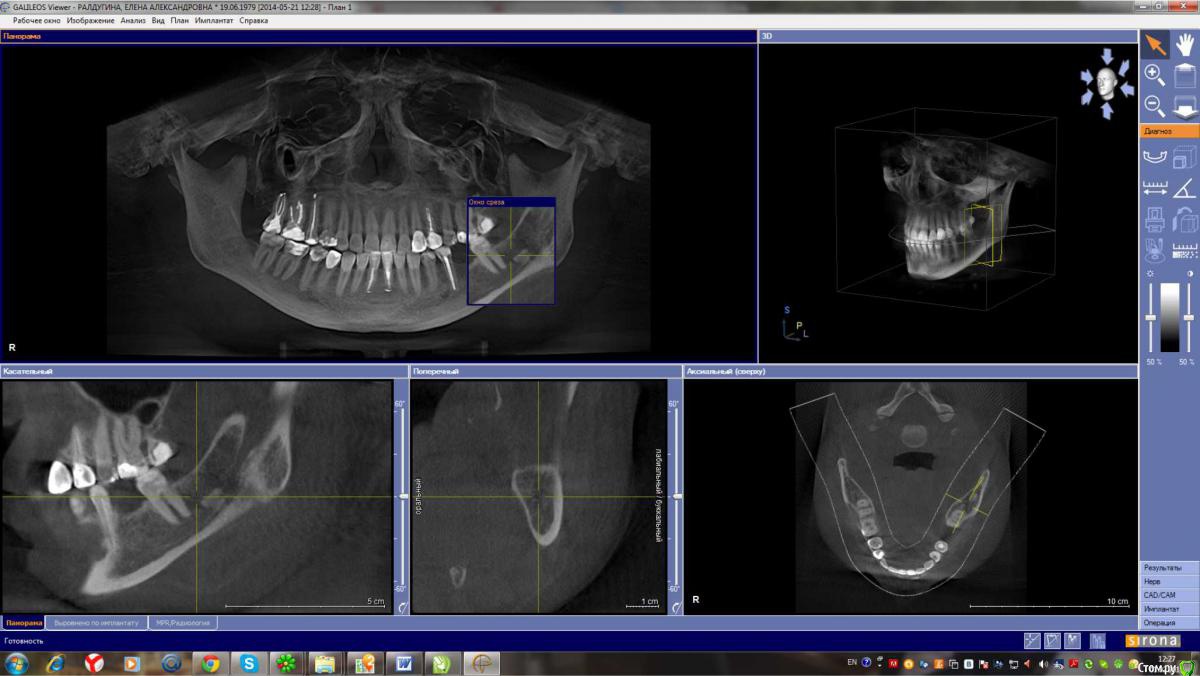

Лена35 Опубликовано 1 февраля, 2015 Автор Поделиться Опубликовано 1 февраля, 2015 кт апрель 2013кт ноябрь 2013последнее кт 2014Удаление сложное было? Не могу прицелиться, чтобы верхний корень было хорошо видно, но он там - в клинике с докторами мы смотрели его, он прямо в десну упирается и жжет там, но не воспаляется, не опухает, не гноится. Может потому что я на нвпс периодически сижу. Или дело вообще не в этих штуках? А как сказали артролог и невролог = миофасцеальный болевой синдром, триггерные точки, повреждение связок при вправлении вывиха... Но почему боль чаще сего я чувствую в области этого верхнего корня? И как долго еще это все будет болеть? Буду благодарна вашим обнадеживающим ответам. Заранее спасибо. Именно от боли острой в этой зоне я мучаюсь после вывиха более четырех месяцев. А до этого в этой зоне я чувствовала периодически , как будто зуб растет и думала, что фантомные боли, я только в сентябре узнала, что эти штуки у меня там есть. Операцию делать не хочу, боюсь осложнений. Но если боль от этого, то жить так тоже не хочу. И как делать операцию, если у меня открытие рта 2,5 см? Ссылка на комментарий

Alejandro Опубликовано 1 февраля, 2015 Поделиться Опубликовано 1 февраля, 2015 Я бы начал с удаления 27-го зуба, далее необходимо разобраться с лимфаденитом (если он ещё будет в стадии обострения). Образование в области нижнечелюстного канала очень похоже на один из корней 38 зуба, я бы предложил его удалить. А открывание рта как давно ограничено? Ссылка на комментарий

Alejandro Опубликовано 2 февраля, 2015 Поделиться Опубликовано 2 февраля, 2015 как Вы по КТ увидели лимфоденит? Выдернуть 27 мне еще никто не предлагал. Поначалу зубы лечатся вроде как эндодонтически.... Про лимфаденит Вы в 26 посте сами сообщили. Сделайте скрин среза в области 27-го, там не очень всё хорошо на верхушках корней. И, кстати, случаи когда зубы приходится удалять без эндодонтии не так уж и редки, к сожалению... Ссылка на комментарий